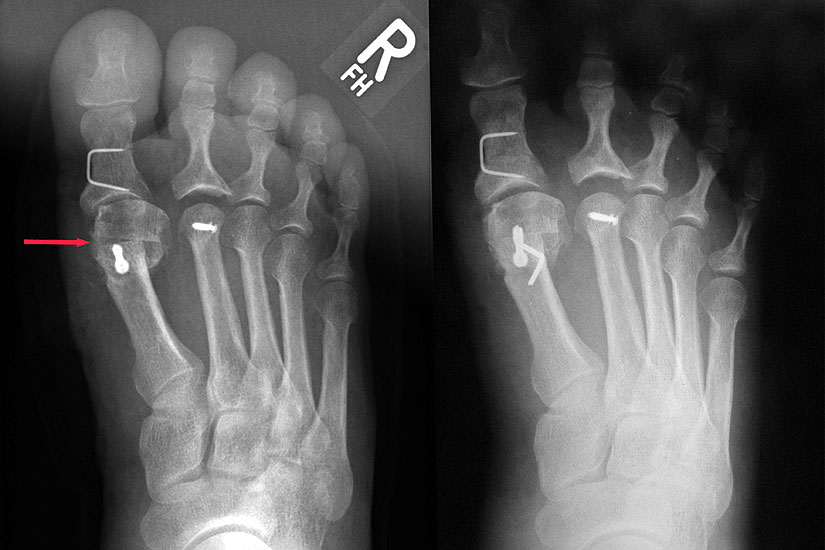

Röntgenkontrollen (Vorfuß in zwei Ebenen) postoperativ und ggf. nach zwei Wochen jeweils ohne Belastung. Abschlusskontrolle zur Dokumentation der knöchernen Konsolidierung nach sechs Wochen unter voller Belastung.

Dislokation des MTK 1 bei zu starker Verschiebung oder/und unzureichender Osteosynthese. Am häufigsten scheint die laterale Verkippung des MTK 1 aufzutreten 19146. Abbildung 27 zeigt eine solche Komplikation am 2. postoperativen Tag. Es folgte die sofortige Revision, mit Schluss der Osteotomie, Austausch der Schraube und Rotationssicherung über einen zusätzlichen Draht.

Die Chevron Osteotomie ist eine der weltweit am häufigsten angewandten Verfahren zur Korrektur einer milden bis mittelgradigen Valgusfehlstellung der Großzehe 1110121319148. Die zahlreichen Publikationen berichten über relativ verlässlich gute und reproduzierbare Ergebnisse. Durch Modifikationen in der Operationstechnik versuchten einige Autoren den Indikationsbereich auf mittelgradige bis schwerwiegende Fehlstellungen auszuweiten 121314. Die Bestimmung des Schweregrades der Fehlstellung erfolgt in erster Linie am belasteten Röntgenbild im dorsoplantaren Stahlengang (siehe Abbildung 1). An dieser Aufnahme können die wichtigsten radiologischen Vermessungen zur Operationsplanung vollzogen werden 112310121312728172930, auch wenn in einigen Studien eine große inter- und intraindividuelle Schwankungsbreite der Messergebisse dargestellt werden konnte 2930. Ebenso zeigt sich eine gewisse Varianz in der Methodik zur Bestimmung des ersten Intermetatarsalwinkels 18282931. Als Grenzwerte für einen milden bis mittelgradigen Hallux valgus werden in der Literatur in relativ weiter Übereinstimmung ein Intermetatarsalwinkel bis maximal 16° und ein Hallux valgus Winkel bis 40° genannt 688. Der DMAA ist radiologisch schwierig zu beurteilen und sollte intraoperativ bei Gelenkeröffnung inspektorisch überprüft werden 2. 2007 verglichen Trnka et al. (2007) die Ergebnisse von vier verschiedenen Nachuntersuchungsgruppen, die sich durch Modifikationen der OP Technik unterschieden: 66 Chevron Operationen von 1991 bis 1992, 100 Chevron Operationen von 1992 bis 1995, 55 Chevron Operationen von 1994 bis 1995 und 89 Chevron Operationen von 2000 bis 2002. So wurde der dorsomediale Zugang 1992 durch einen streng medialen Zugang mit L-förmiger Kapsulotomie ersetzt. 1992 wurde das laterale Release über einen dorsalen Zugang eingeführt mit Perforation der lateralen Kapsel längs zwischen Metatarsale 1 und fibularem Sesambein, sowie vertikal im Verlauf der Gelenklinie ohne Ablösung des Adduktors oder Durchtrennung des intermetatarsalen Bandes. Zwischen 1994 und 2000 wurde eine temporäre Fixation mit einem Kirschnerdraht durchgeführt. Seit 2000 wird die Osteotomie mit einer kanülierten Kompressionsschraube fixiert. Insbesondere die Einführung des lateralen Release führte zu einer signifikanten Verbesserung des Hallux valgus- und Intermetatarsalwinkels, ohne vermehrt Probleme mit einer avaskulären Nekrose des MTK 1 zu bekommen. Die Einführung einer Osteosynthese mittels Kirschnerdraht zeigte im follow up nach 34 Monaten gegenüber der lediglich manuellen Einstauchung des distalen Fragments, wie in der Originalarbeit von Austin beschrieben, eine geringere Rate an Korrekturverlusten und Dislokationen des ersten Metatarsaleköpfchens. Durch die Verwendung einer Schraube konnte das Indikationsspektrum hinsichtlich Schweregrad des Hallux valgus erweitert werden. Der Vergleich einer 2-Jahres- und eines 5-Jahres-Nachuntersuchung zeigte gegenüber der präoperativen Untersuchung eine Verbesserung des IM-Winkels von 13° auf 8° respektive 9°. Der HV-Winkel konnte von durchschnittlich 29° auf 15° respektive 16° reduziert werden. Ergebnisse, welche auch die langfristige Zuverlässigkeit der Chevron-Osteotomie in der Behandlung des milden bis mittelgradigen Hallux valgus belegen.